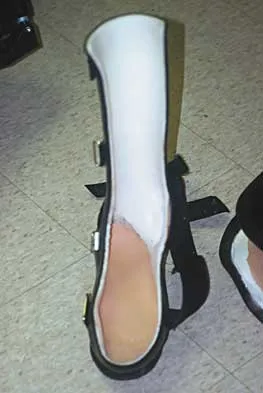

A 40-year-old man has a painless mass around his left ankle. He notes minimal growth over the past year. An MRI scan is shown in Figure 73a, and biopsy specimens are shown in Figures 73b and 73c. What is the most likely diagnosis?